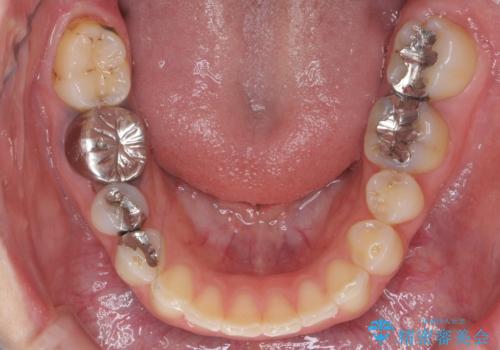

上顎2番は矮小歯だったのをセラミックで被せています。

- 矯正治療85万円 補綴治療16万円(emaxクラウン、仮歯)費用は治療当時の料金となります

口唇の突出感がなくなり、理想的な横顔になりました。

虫歯治療は、他院で保険治療で行なって頂いています。